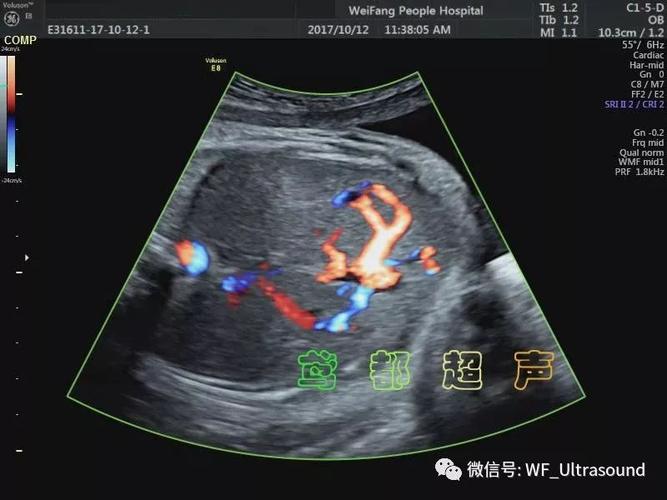

胎儿静脉导管超声图像

胎儿静脉导管超声图像,胎儿动脉导管超声图解

胎儿静脉导管超声切面

胎儿静脉导管超声图片

静脉导管超声图